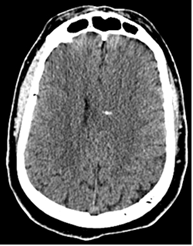

L’analyse des données du TR-DGU de 2017 nous montre plusieurs éléments intéressants pour la radiologie. Par exemple, le patient nécessitant un body-scanner à la Citadelle l’a obtenu en moyenne 17 minutes après son arrivée au Trauma center pour une moyenne de 22 minutes dans l’ensemble des hôpitaux du registre. Autre exemple, 96 % des patients avec un score de Glasgow < 14 ont eu une évaluation par scanner cérébral. Cette professionnalisation de l’activité est stimulante pour les équipes avec, comme objectif, l’amélioration continue de l’expertise des différents maillons de la prise en charge.

Figures ci-dessus : Accident de moto sur circuit, intubation sur place. Le body-scanner révèle un hématome sous dural supra-tentoriel gauche, de multiples petites contusions cérébrales hémorragiques, une fracture isolée du condyle occipital droit, une contusion du rein gauche avec lame d’hématome sous capsulaire.